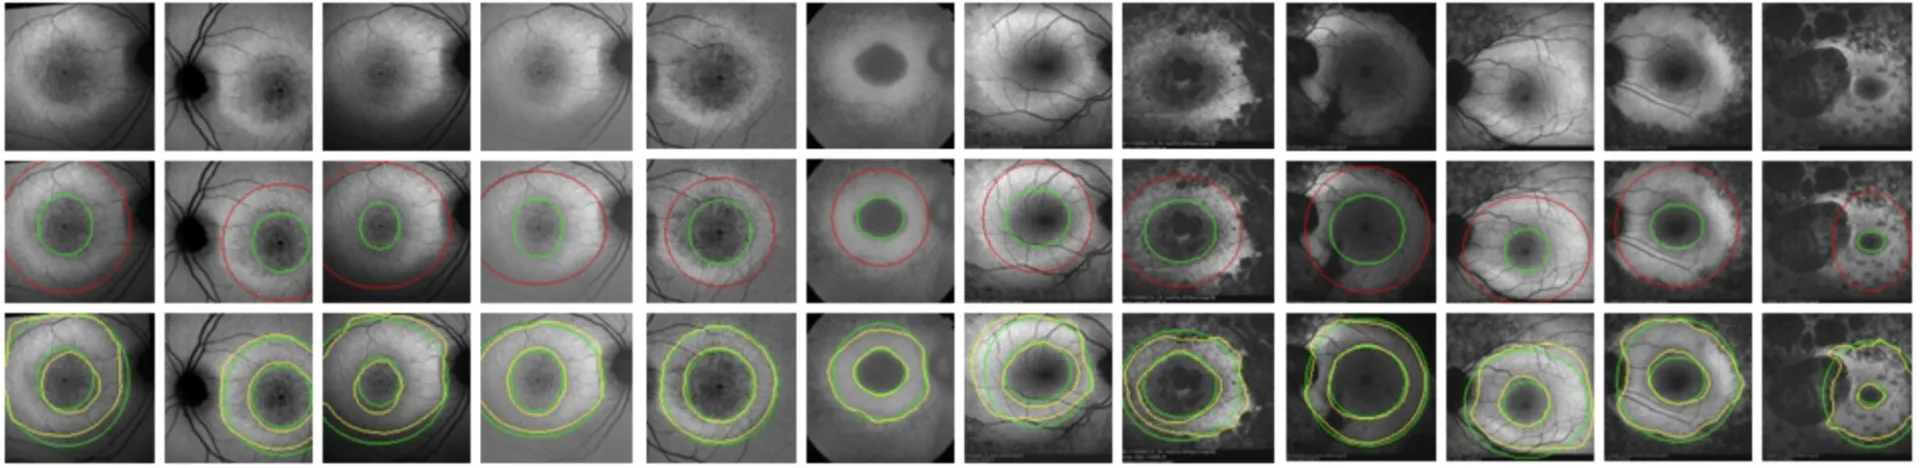

Our problem domain includes both basic science (e.g. image formation and acquisition), algorithmic design and clinical applications (e.g. measures of pathological processes). Our scope of imaging is broad and includes the study of image formation, denoising, segmentation, feature extraction, and anatomo-physiological modeling. We are interested in imaging structures at the molecular, cellular, tissue, and organ levels of analysis.

We have strong expertise in multiple methodological techniques, such as wavelet decomposition, speckle tracking, texture analysis, variational segmentation, parametric deformable models, and PET reconstructions. We deal with a wide range of imaging modalities, including 3D real-time echocardiography, lung computed tomography (CT), ultrasound, magnetic resonance imaging (MRI), and positron emission tomography (PET).